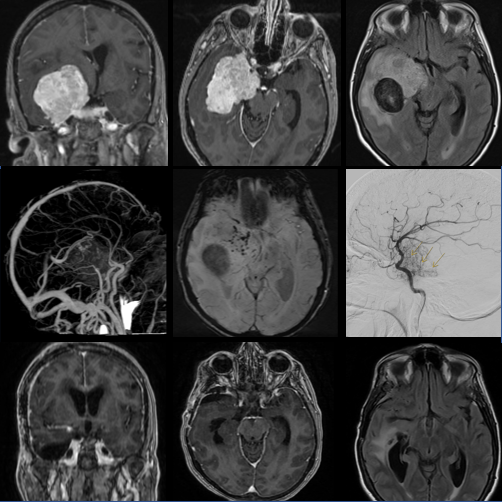

Imaging performed demonstrated a large, avidly-enhancing lesion centered along the right tentorium and cavernous sinus (A,B). FLAIR-imaging demonstrated associated vasogenic edema extending posteriorly in the temporal lobe (C). 3-D reconstructed CT angiography demonstrates the displacement of the right middle cerebral vessels (arrow), and susceptibility-weighted imaging demonstrates the internal vascularity of the tumor and a calcified component posteriorly (E, asterisk). Formal angiography demonstrates the tumor blood supply from the tentorium (F, arrows).

A right cranio-orbito-zygomatic approach was performed to resect the lesion. The patient had diplopia in the early postoperative period that resolved  by 4-month follow-up. Pathology returned as W.H.O. Grade 2 Meningioma with an elevated MIB-1 index (17.9%). Focal islands of erythroid-dominant hematopoietic elements were scattered throughout, consistent with extramedullary hematopoiesis. Copy number analysis identified broad losses of 1p and 6q, as well as focal losses of 7p and 22q, including single copy loss of NF2, consistent with a molecularly integrated grade 2 diagnosis (Driver et al., Neuro-Oncology, 2022).

This case highlights the unique histopathology and cytogenetic features of a radiation-induced meningioma associated with childhood cranial irradiation for ALL. Radiation-induced meningiomas are a well-known late complication of childhood radiation (Al-Mefty, J. Neurosurg, 1990) with a unique genetic landscape (Agnihotri, Nat Commun, 2017) and relatively aggressive natural history compared to sporadic meningiomas. This lesion demonstrated concerning radiographic and histopathological features and will need to be followed indefinitely for recurrence.